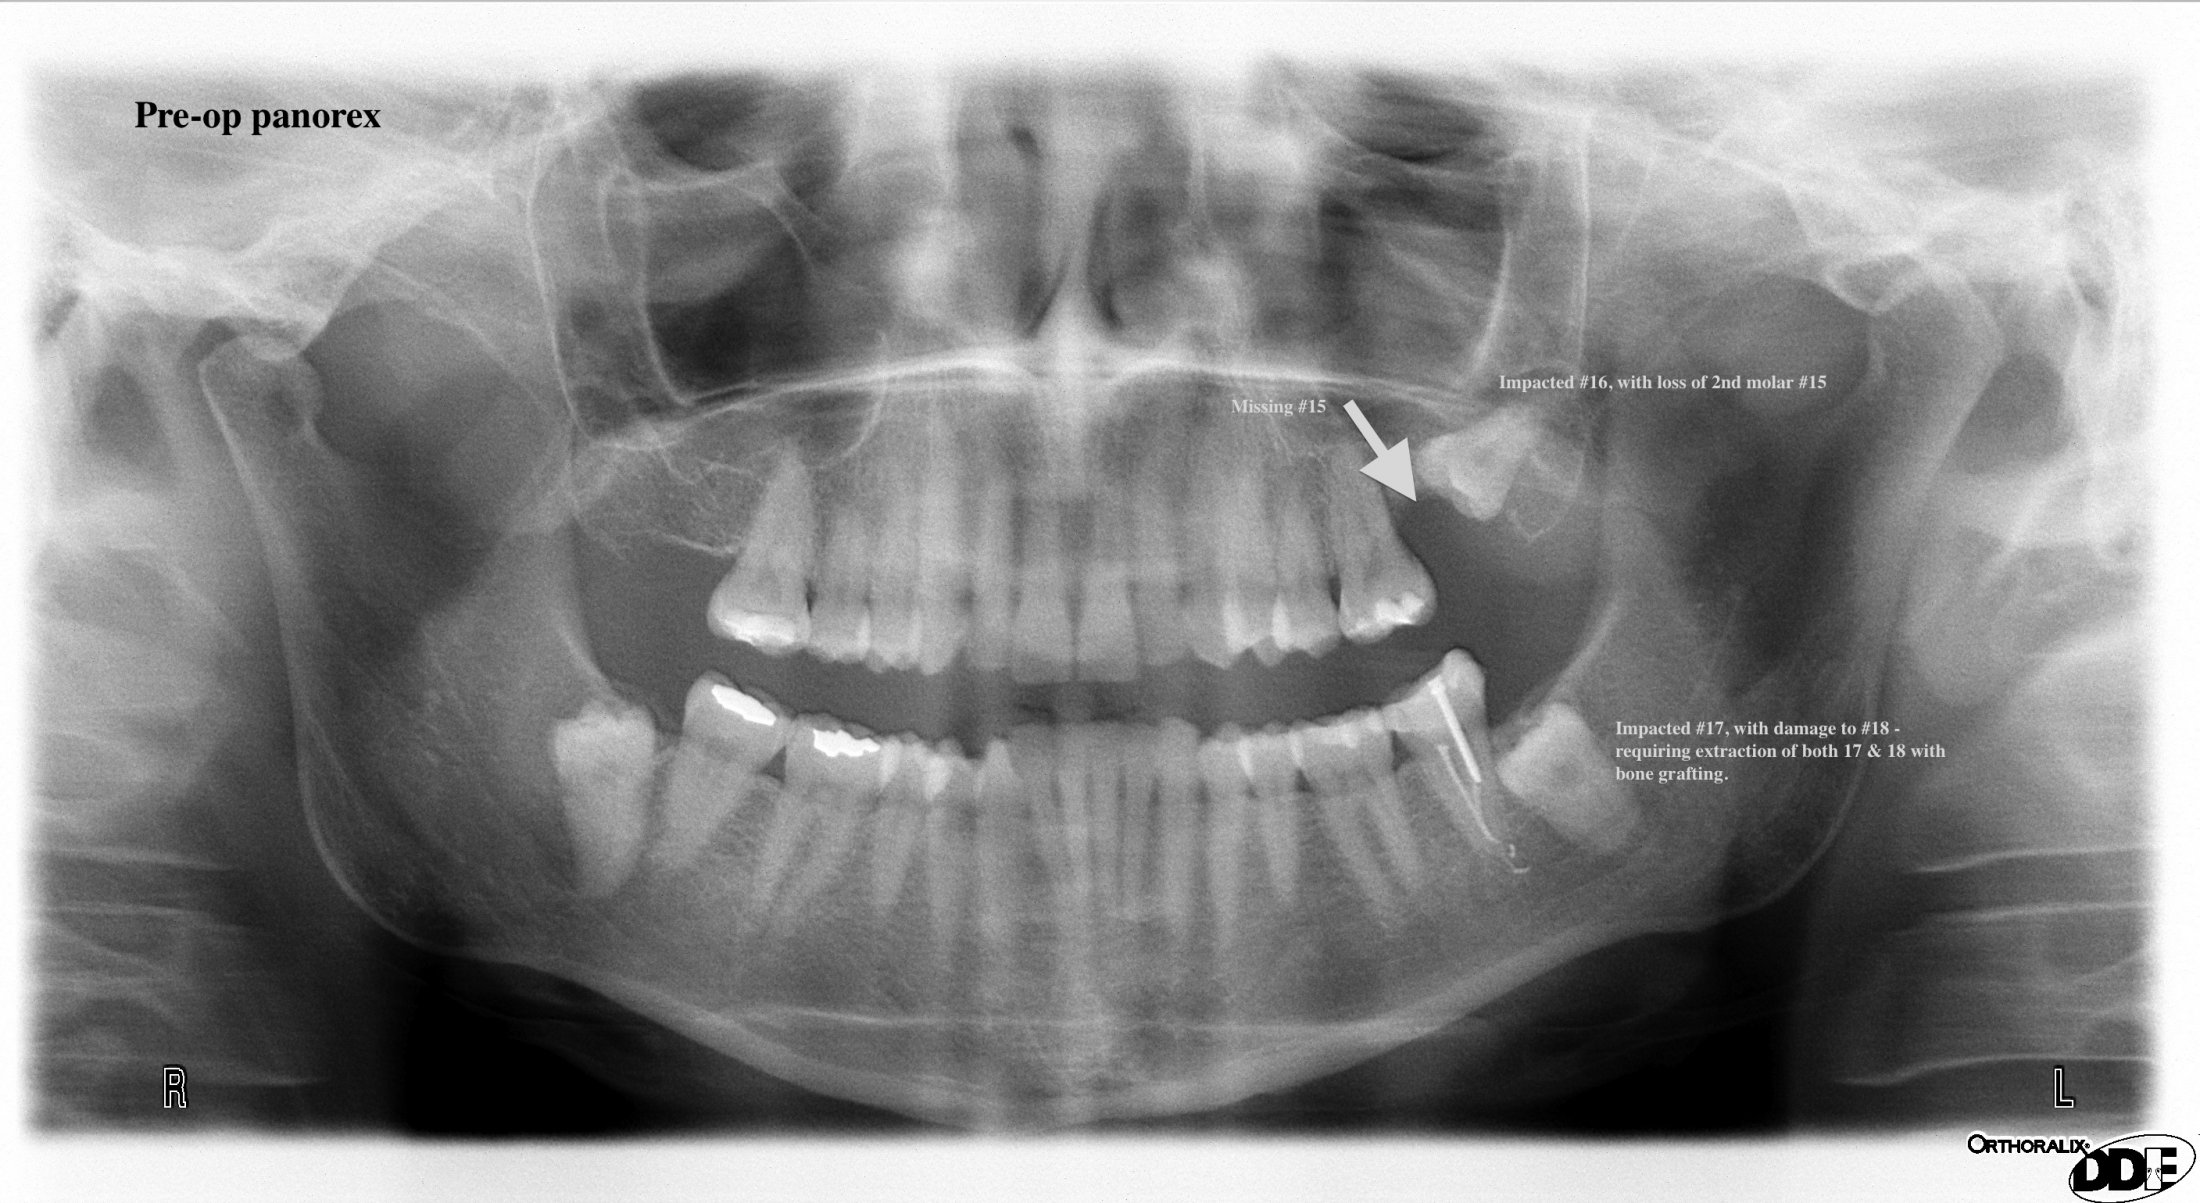

Below is the before and after panorex x-rays of a patient that presented to me for extraction of her third molars on the left side. She had already lost #15 due to damage from third molars #16. Interestingly she was having sinus issues – which they did not attribute to her third molar. After the extraction of #16 her sinusitis improved! Also we had to extract #18 due to damage from her impacted #17. Hence she ended up losing both her third molars 16 & 17, in addition to her 2nd molars #15 & 18. If she would have just extracted her third molars as a teenager, she would not have lost those two additional adult teeth.